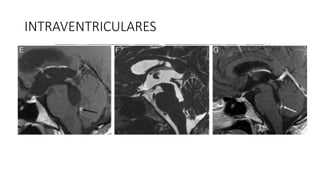

INTRAVENTRICULARES

• #41 Cisticerco intraventricular. Estudio de TC sin contraste (A), que muestra una lesión quística en el IV ventrículo. Imágenes de RM potenciadas en T1 con gadolinio (B) y en T2 (C) en el plano axial, así como secuencias en T2 de alta resolución (D) y T1 con gadolinio

• #42 (E) en el plano sagital, que muestran una lesión quística intraventricular obstruyendo el IV ventrículo, con un nódulo mural inferior que realza con el gadolinio (flecha). Control de RM posterior al tratamiento anticesticida (F y G), que muestra disminución del tama˜no de la lesión intraventricular, a la vez que persiste una mínima captación de gadolinio en el margen inferior del IV ventrículo (flecha